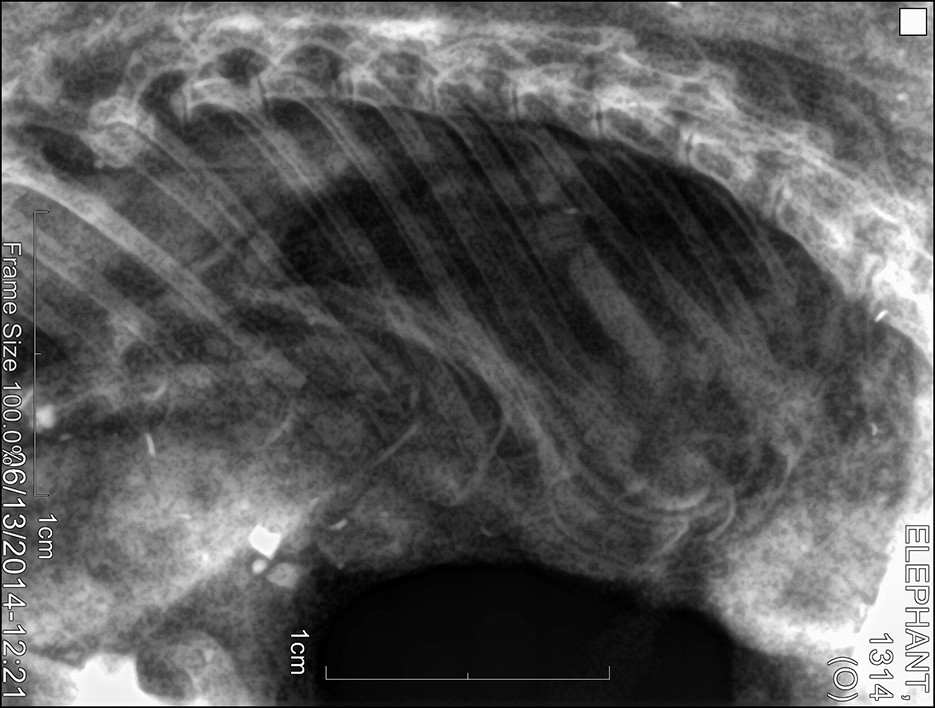

Der von ihm geforderte Beweis scheint inzwischen zumindest teilweise erbracht zu sein. Wissenschaftler und Forscher des Pha Woh Hospitals im Mae Sot Distrikt haben Überreste solcher Wasserelefanten untersucht. Die Röntgenaufnahmen der kleinen Körper zeigen, daß diese winzigen Wesen eine Knochenstruktur haben, welche jener der ausgewachsenen asiatischen Elefanten gleicht.

Röntgen1 Röntgen2 Röntgen3

(Original-Röntgenaufnahmen des untersuchten Exemplars)